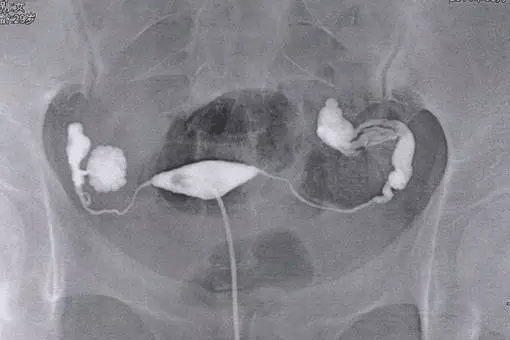

③、然后只需要在X线透视下观察造影剂流经宫腔,再慢慢注入碘油,观察子宫及流经输卵管的情况,此时会拍摄一张照片然后会继续推入碘油,5--10分钟后继续拍片;

④、间隔一天时间后会在同部位拍摄,如果双侧输卵管不通那么久不会有游离的碘海醇,如果有少量碘海醇那么确定为输卵管通而不畅。